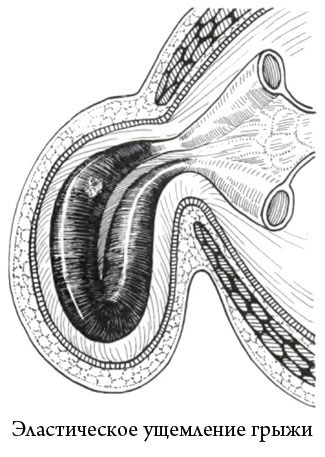

1. încălcarea elastică

ciupirea elastică are loc atunci când o creștere bruscă a presiunii abdominale. Motivele pentru acest lucru este simplu: tuse, strănut, entorse bruște ale corpului, ridicarea de greutati, efortul de defecatie, etc ...

Cu varietate de încălcări în sacul herniar afară mai mult conținut decât de obicei, și nu poate veni înapoi. organe la stânga a fost transferat de inel herniar are loc în acesta anoxia (ischemie), care, în lipsa asistenței adecvate devine țesuturi de necroză (necroză).

atribut indispensabil al încălcării elastice - herniar foarte îngust.